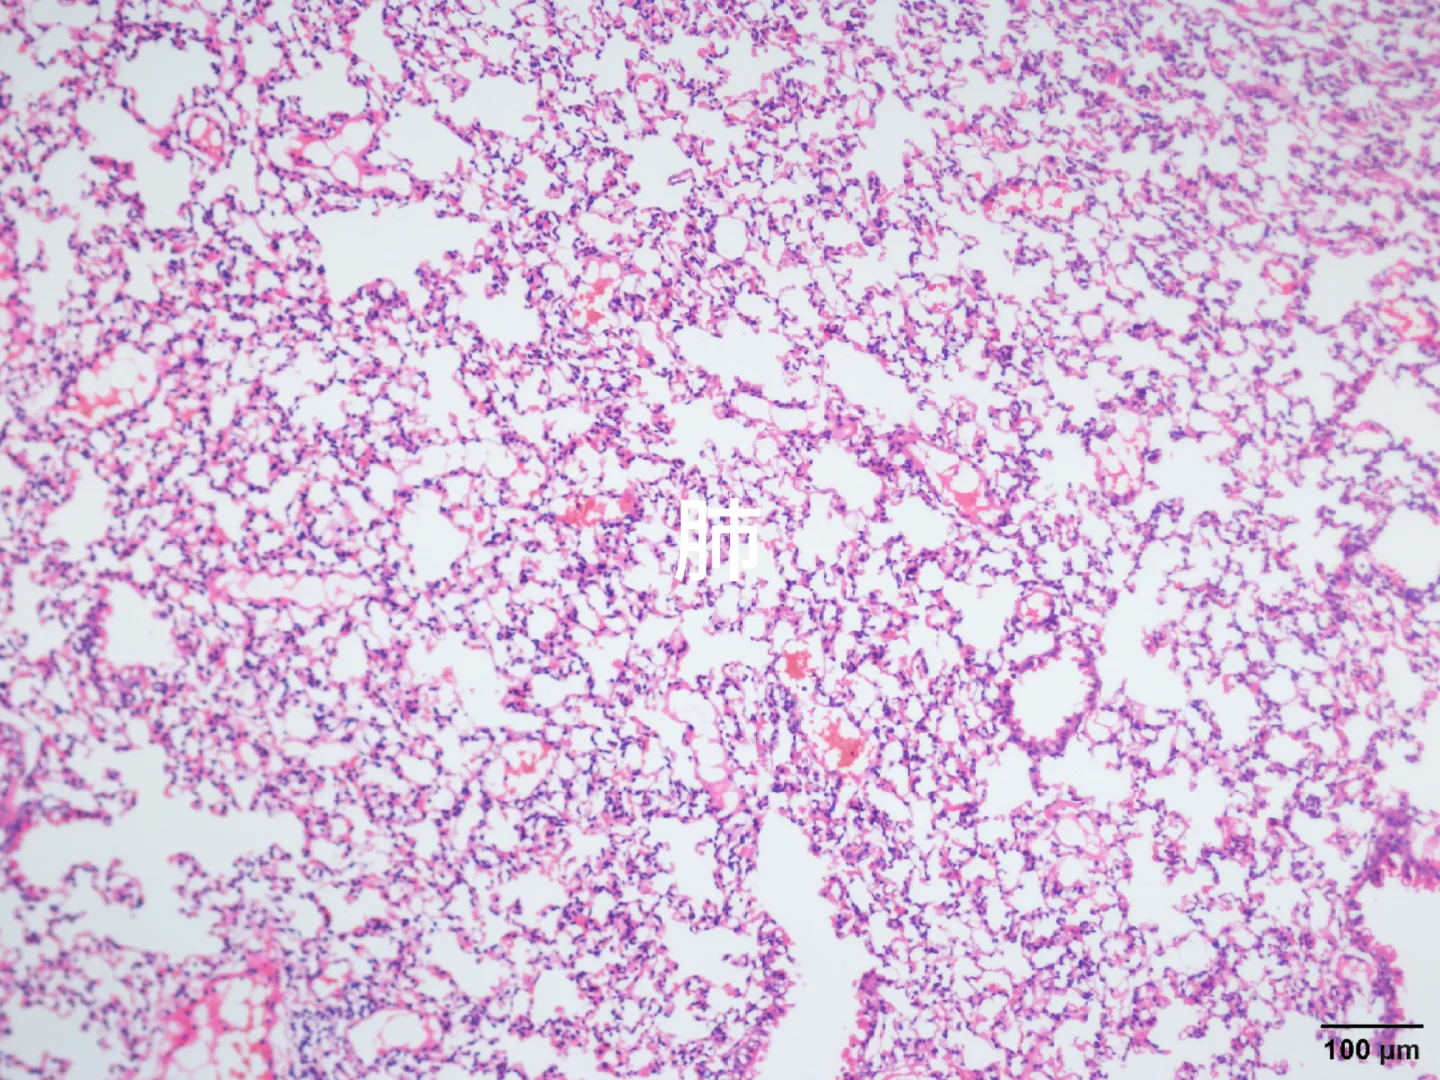

心肝脾肺肾肿瘤HE染色

由于我取了组织后用多聚甲醛固定,然后不小心放-80°一天,后面又放回四度,有没有大神帮忙看看能不能用!